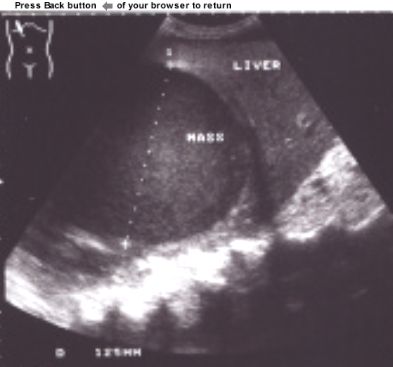

This patient had an

abdominal ultrasound. A single, round,

hypoechoic, homogeneous, well

defined mass was demonstrated in the right liver lobe. The size of the

mass was 12,5 cm. The borders of the mass was smooth and clearly separated

from liver parenchyma. The rest of the liver parenchyma was normal and

examination of the rest of the abdomen did not reveal any other

pathology.